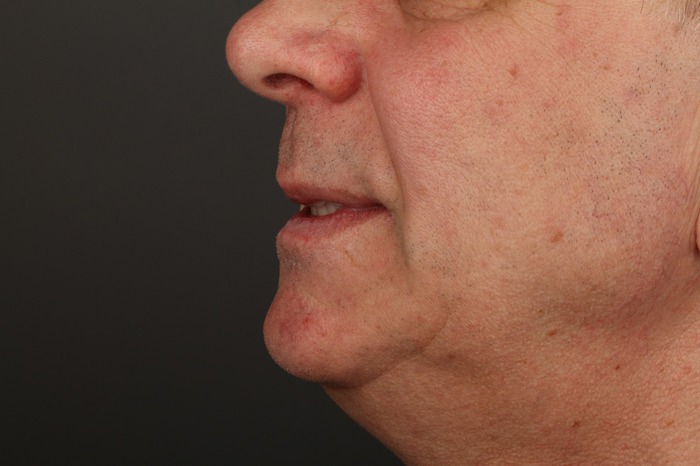

Хорошо выглядят и блестят, по фото с телефона мало что понятно, но в полости рта они смотрятся гораздо интересней.

Нижний протез плотно, даже с небольшим давлением, прилегает. Верхний через пару месяцев будем делать такой-же.

Ну и лучшая награда для меня — улыбка пациента!